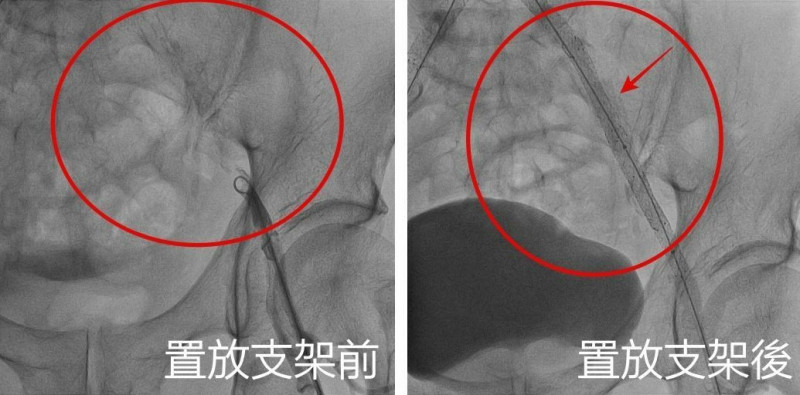

經與患者討論後,決定安排導管手術置放支架,先從患者的鼠蹊部及手臂動脈置放導管,之後在血管腔打通腹主動脈阻塞部位,並將5支支架置放在右髂動脈,一舉改善阻塞問題,患者術後5小時就可下床走動,疼痛明顯改善,術後第5天就康復返家,回診時還透露原本勃起障礙的問題也一併大幅改善,頻頻感謝醫師。